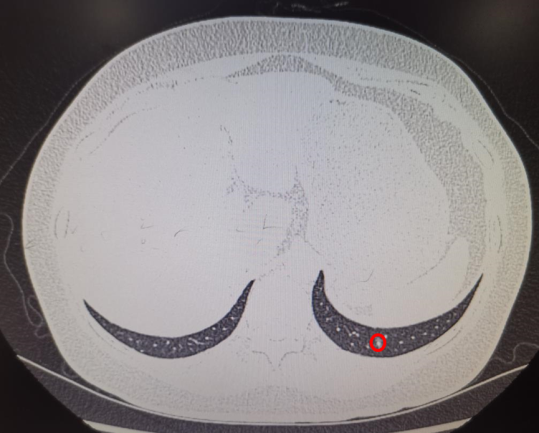

其中消融患者的肺结节位于左肺下叶外基底段24级支气管,膈肌腱部后缘,大小8mm,受呼吸运动影响大,技术难度极大,堪称肺消融治疗的“珠穆朗玛峰”。柳教授团队顺利完成了该例患者治疗,填补了福建省多项肺小结节诊断及治疗技术的空白,同时意味着,那些心肺功能无法耐受开放或者胸腔镜肺小结节手术的患者以及双肺多枚肺小结节需要同时手术的患者有机会获得更多精准且彻底治疗的可能性。

ENB-MWA患者术前小结节位置及消融术后3天复查CT见病灶区域成消融后炎性改变(完全覆盖结节位置)。